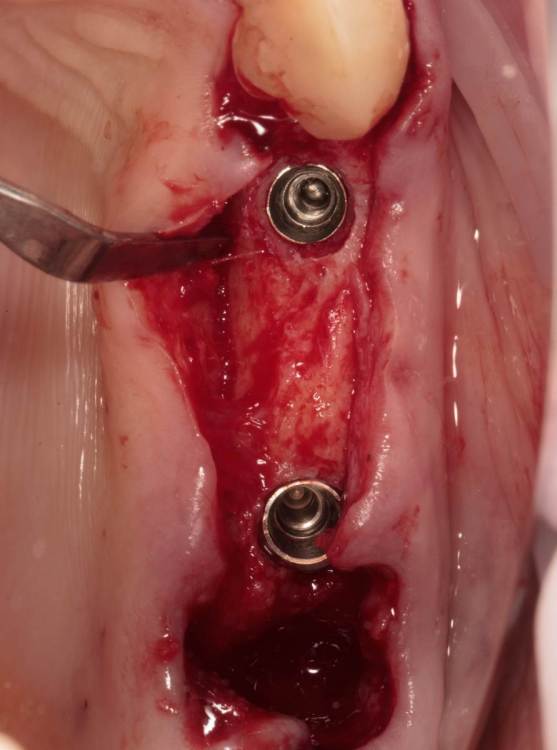

Женька Опубликовано 24 июля, 2023 Поделиться Опубликовано 24 июля, 2023 Тема ради одной фотки конечно, но всё-таки вопрос есть. Говорят МСТ профайлер не задевает стенки имплантата. Кмк, всё-таки задевает. Или всё-таки кажется? По кейсу: 2 имплантата, оба по шаблону. Черт дёрнул пройти глубже чем планировал в 1.6, фрезой перфо не создал, но кортикалку в ноль убрал. И при отслойке всё-таки порвал немного. Тампонировал губками, пробы отрицательные. Вроде нигде не перемудрил в этот раз, @АнтонТЛТ ? 3 Ссылка на комментарий

Raystom Опубликовано 24 июля, 2023 Поделиться Опубликовано 24 июля, 2023 @Женькакажется. Там юбка направляющего пина не даёт портить стенки. Ссылка на комментарий

Женька Опубликовано 24 июля, 2023 Автор Поделиться Опубликовано 24 июля, 2023 @Raystom я про эти участки Ссылка на комментарий

Raystom Опубликовано 24 июля, 2023 Поделиться Опубликовано 24 июля, 2023 @Женька хотя да, если присмотреться, то есть небольшое снятие фаски шейки по внутреннему контуру. Ссылка на комментарий